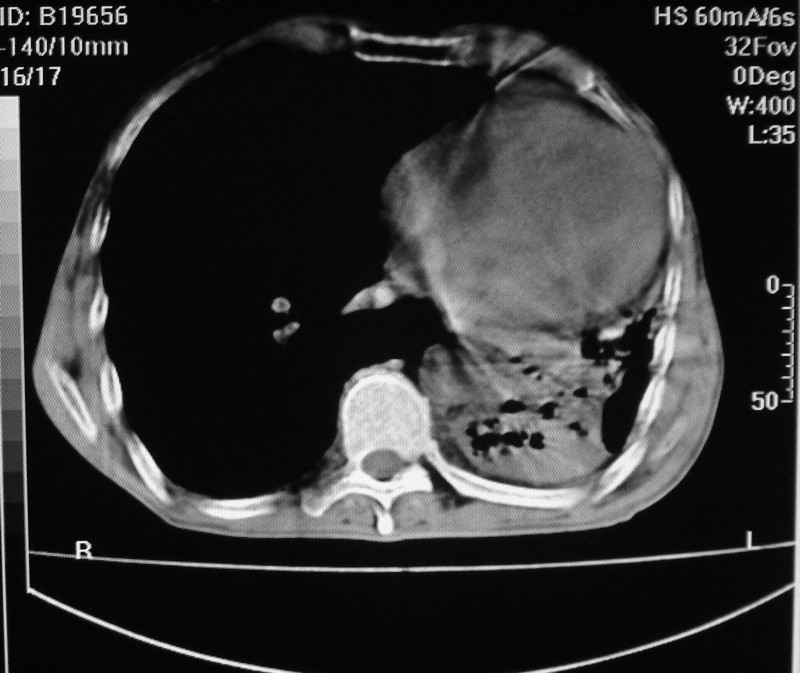

以下是引用杀毒软件在2008-12-10 21:28:00的发言:[br]考虑------双肺继发性肺tb-----左肺下tb毁损肺表现可能性大-----建议气管镜